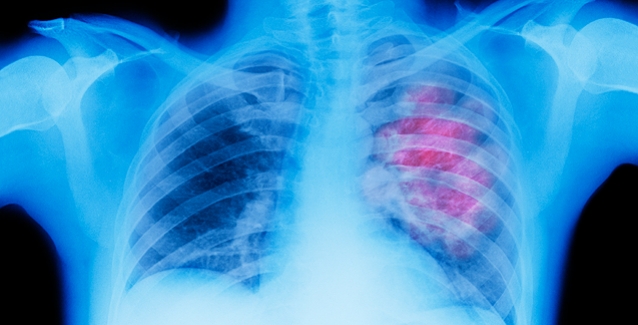

Ένας βήχας τον τελευταίο χρόνο είχε προβληματίσει τον Γιώργο Βασιλείου και τη σύζυγό του. Αποφάσισαν να κάνουν αξονική, η οποία έδειξε «μαύρισμα» στον πνεύμονα και ένας φίλος γιατρός τους προέτρεψε να προβούν σε ενδελεχή ιατρικό έλεγχο.

Οι εξετάσεις έγιναν σε δημόσιο νοσοκομείο και ύστερα από 20 μέρες βγήκαν οι απαντήσεις. Ο «ταξίαρχος Θεοχάρης» έπρεπε να κάνει εσπευσμένα εισαγωγή στο Αντικαρκινικό Νοσοκομείο Μεταξά, στον Πειραιά.